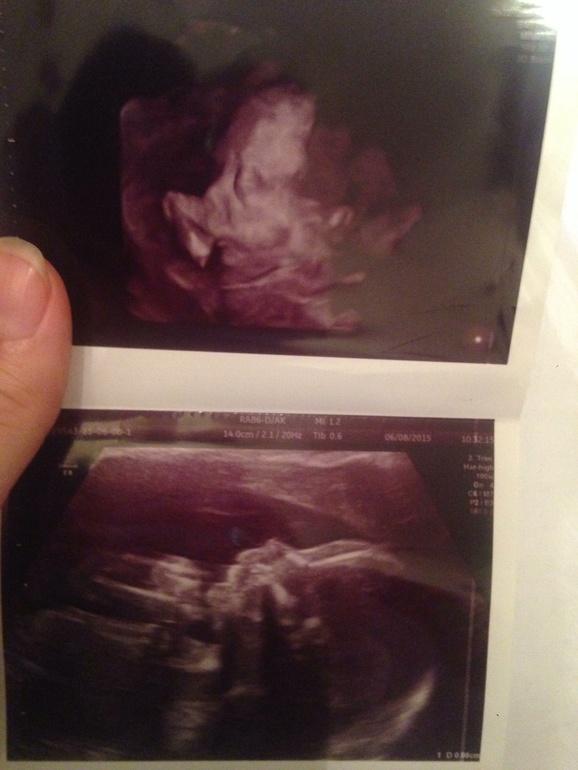

Делать или нет ? Сходили на узи! Развеяли страхи. Фото прилагается.

дааа))) спасибо ))) сегодня ходила на узи к другому хорошему специалисту) все в норме сказал)))